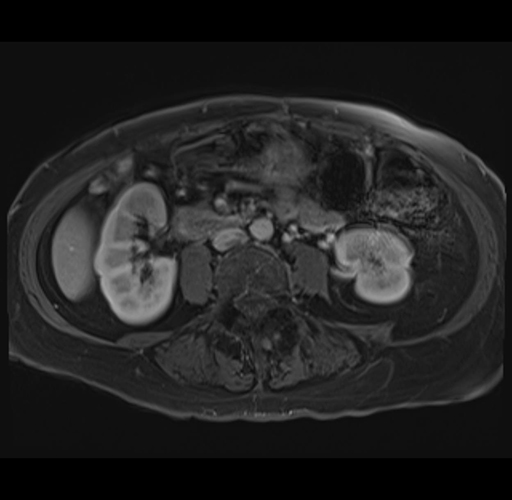

MRI T1